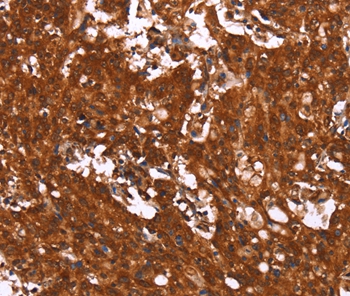

Immunohistochemical staining of human tonsil shows strong cytoplasmic positivity in non-germinal center cells.